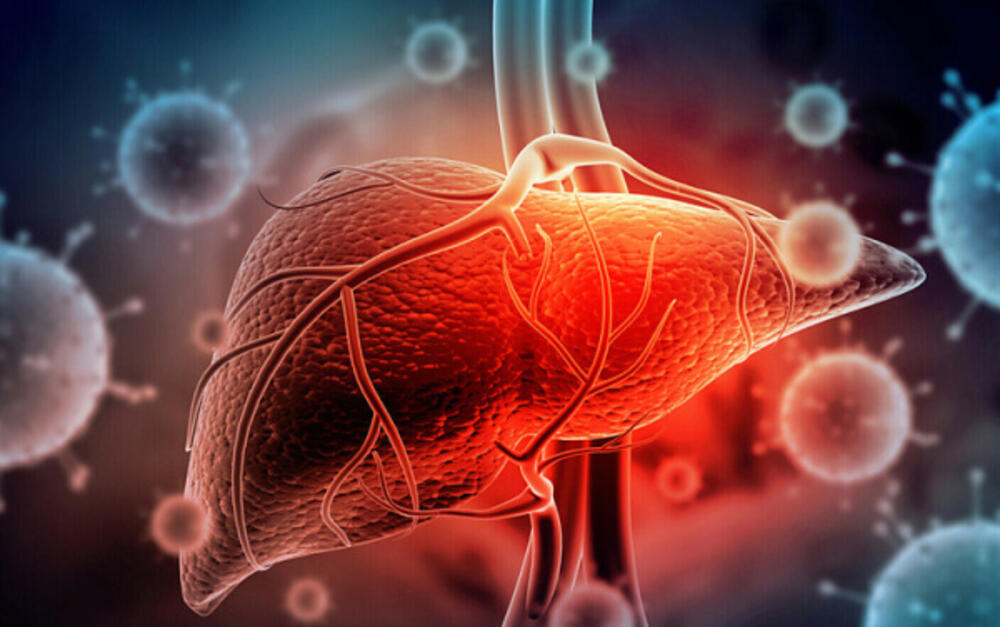

ڈبلیو ایچ او نے ہیپاٹائٹس ڈی کو جگر کے کینسر کی ایک اہم وجہ قرار دیا ہے۔ صحت کے عالمی ادارے نے اس حوالے سے فوری اقدامات پر زور دیا ہے۔ یہ بیان عالمی یومِ ہیپاٹائٹس کے موقع پر جاری کیا گیا۔

ہیپاٹائٹس ڈی صرف اُن افراد کو متاثر کرتا ہے جو پہلے ہی ہیپاٹائٹس بی میں مبتلا ہوں۔ یہ وائرس جگر میں شدید سوزش اور نقصان پیدا کرتا ہے۔ ڈبلیو ایچ او کے مطابق اس وائرس سے کینسر کا خطرہ دو سے چھ گنا بڑھ جاتا ہے۔

ڈبلیو ایچ او کے تحقیقی ادارے ”آئی اے آر سی” نے ہیپاٹائٹس ڈی کو ”گروپ 1 کارسینوجن” میں شامل کر لیا ہے۔ گروپ 1 اُن عوامل پر مشتمل ہے جن کے بارے میں سائنسی ثبوت موجود ہوں کہ وہ کینسر پیدا کرتے ہیں۔

ہیپاٹائٹس ڈی کے پھیلاؤ کو روکنے کا واحد مؤثر طریقہ ہیپاٹائٹس بی کی ویکسین ہے۔ اس کی وجہ یہ ہے کہ ڈی وائرس صرف بی وائرس کی موجودگی میں فعال ہوتا ہے۔

ڈبلیو ایچ او کے مطابق دنیا بھر میں 30 کروڑ افراد ہیپاٹائٹس بی، سی یا ڈی سے متاثر ہیں۔ ان میں سے ہر سال 13 لاکھ افراد جگر کے کینسر یا دیگر پیچیدگیوں سے جان کی بازی ہار جاتے ہیں۔ حکومتوں سے اپیل کی گئی ہے کہ وہ ہیپاٹائٹس کے علاج کو اپنی قومی ترجیحات میں شامل کریں۔ بصورتِ دیگر جگر کے امراض اور اموات میں اضافہ ہو سکتا ہے۔